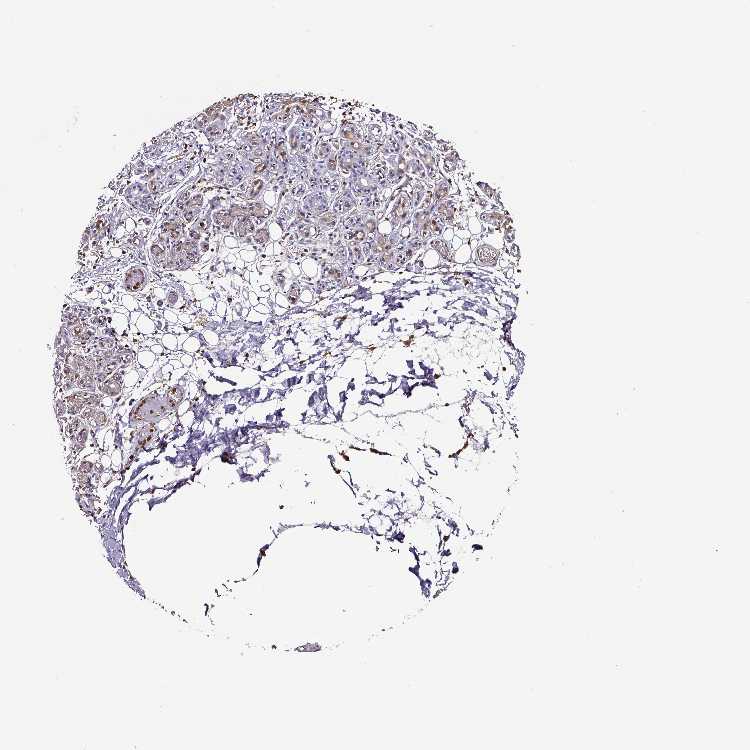

SALIVARY GLAND - Antibody stainingi

Antibody staining in the annotated cell types in the current human tissue is reported as not detected, low, medium, or high, based on conventional immunohistochemistry profiling in selected tissues. This score is based on the combination of the staining intensity and fraction of stained cells.

Each image is clickable and will lead to virtual microscopy that enables deeper exploration of all samples and also displays staining intensity scores, fraction scores and subcellular localization as well as patient and tissue information for each sample.

Antibody HPA051235Antibody CAB018584

Glandular cells LowLow